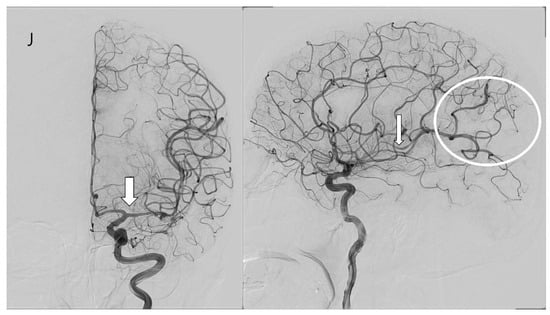

3.4. Case Illustration